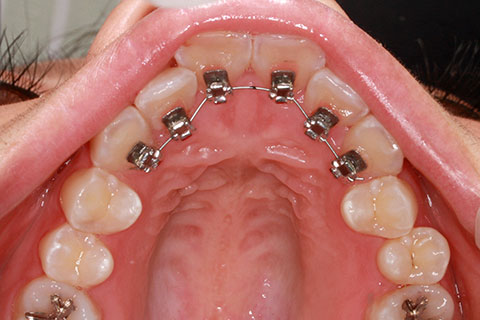

フルリンガル矯正1(上下の歯を舌側矯正で治療)

治療前

治療中

治療後

- 年齢・性別

- 33歳女性

- 治療期間

- 2年0ヶ月

- 抜歯

- 上顎4番抜歯。下顎5番欠損。

- 治療費

- 120万円(税込み)

- 備考

- フルリンガル矯正

- 治療内容

- 上顎前歯の叢生改善および下顎前歯の空隙閉鎖

- 施術の副作用(リスク)

- 装置が裏側について、目視ができないため、しっかりとブラッシングができているかどうかわかりにくい。